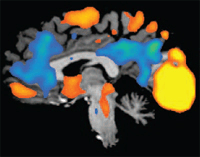

Influence of meditation on anti-correlated networks in the brain.